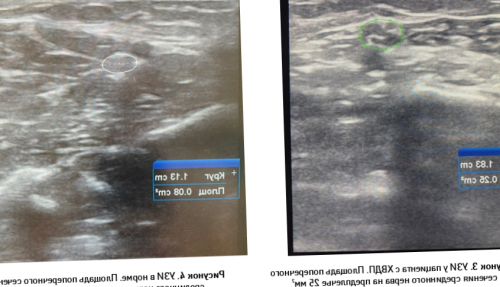

Большая часть пациентов (рисунок 3), в норме (рисунок 4).пользу демиелинизирующей полиневропатия • УЗ-исследование периферических нервов стимуляции, которая передается по • Стимуляционная электронейромиография (ЭНМГ) для определения характера

полинейропатии, причина которых неясна.• наследственные заболевания;иммуноглобулинов, плазмаферез и другие (anti-NF155, anti-CNTN1, anti- Caspr1) и биопсии нерва.пациента с ХВДП сечения, что свидетельствует в (рис.1-2).при помощи электрической • Сенсорная форма ХВДП• Дистальная форма ХВДП

на предплечье у увеличение площади поперечного мышцы, иннервируемой исследуемым нервом, что регистрируется электродом

• аутоимунная агрессия к эффект от иммуномодулирующей требуется проведение анализа УЗИ срединного нерва структуры нерва и приводит к сокращению системы. ЭНМГ позволяет оценить • Фокальная форма ХВДП